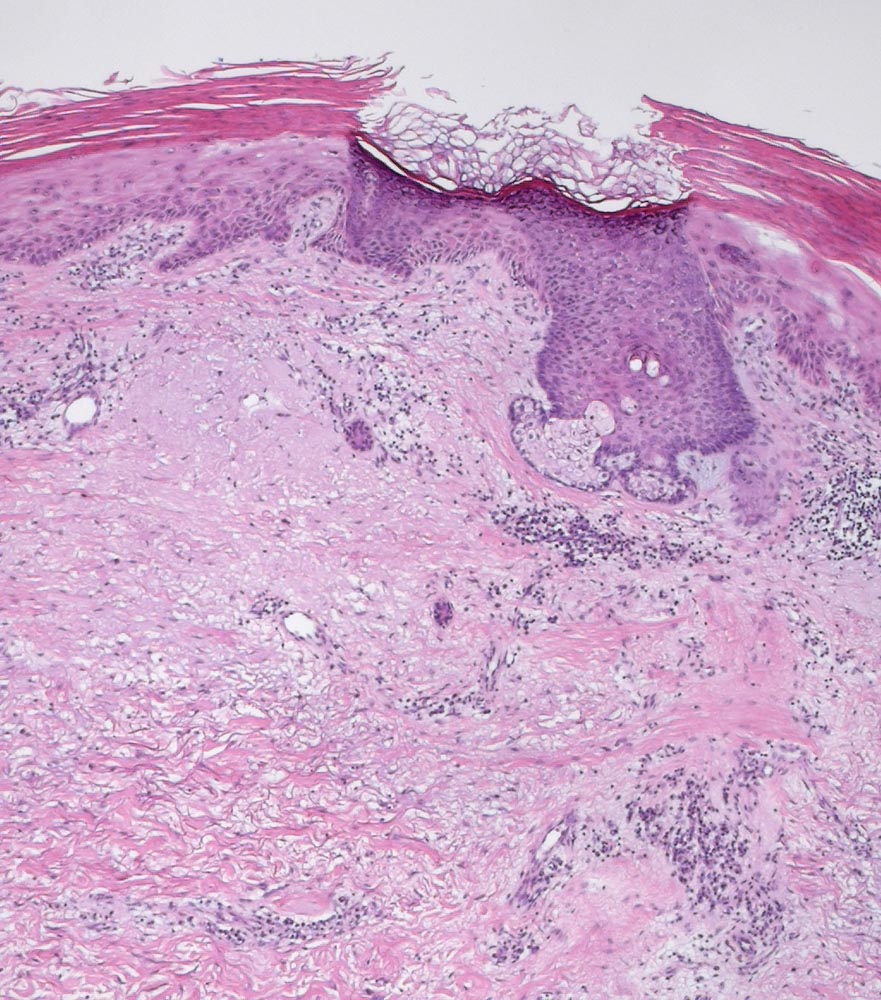

Solare Präkanzerose (Keratose) mit leichter Epitheldysplasie

Hyper-parakeratotisch verhornende akanthotisch verbreiterte Epidermis und schwere solare Elastose. Das dysplastische Epithel ist deutlich heller und zeigt eine gestörte Ausreifung. Die Keratinozyten haben vergrösserte atypische hyperchromatische Zellkerne. Sehr gut sichtbar ist hier die Aussparung der Hautadnexe. Das Epithel des Haarfollikels zeigt keine Dysplasie und die darüberliegende Epidermis zeigt eine normale korbgeflechtartige Verhornung.

Nachexzisat nach Exzision eines atypischen Fibroxanthoms an der Stirn.